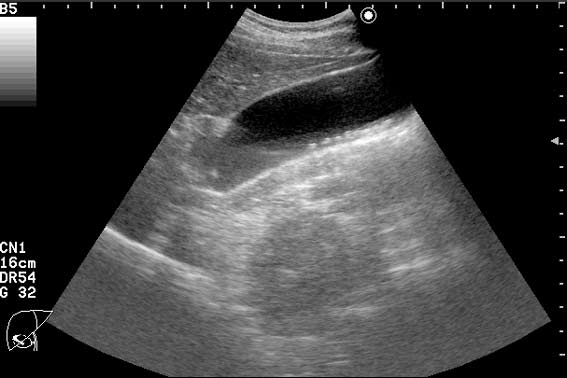

Пациент с приступом резких болей в животе, тошнотой, рвотой.

"Горошек" в пузыре и холедохе.

Да, ЖКБ, ходедохолитиаз, холецистолитиаз